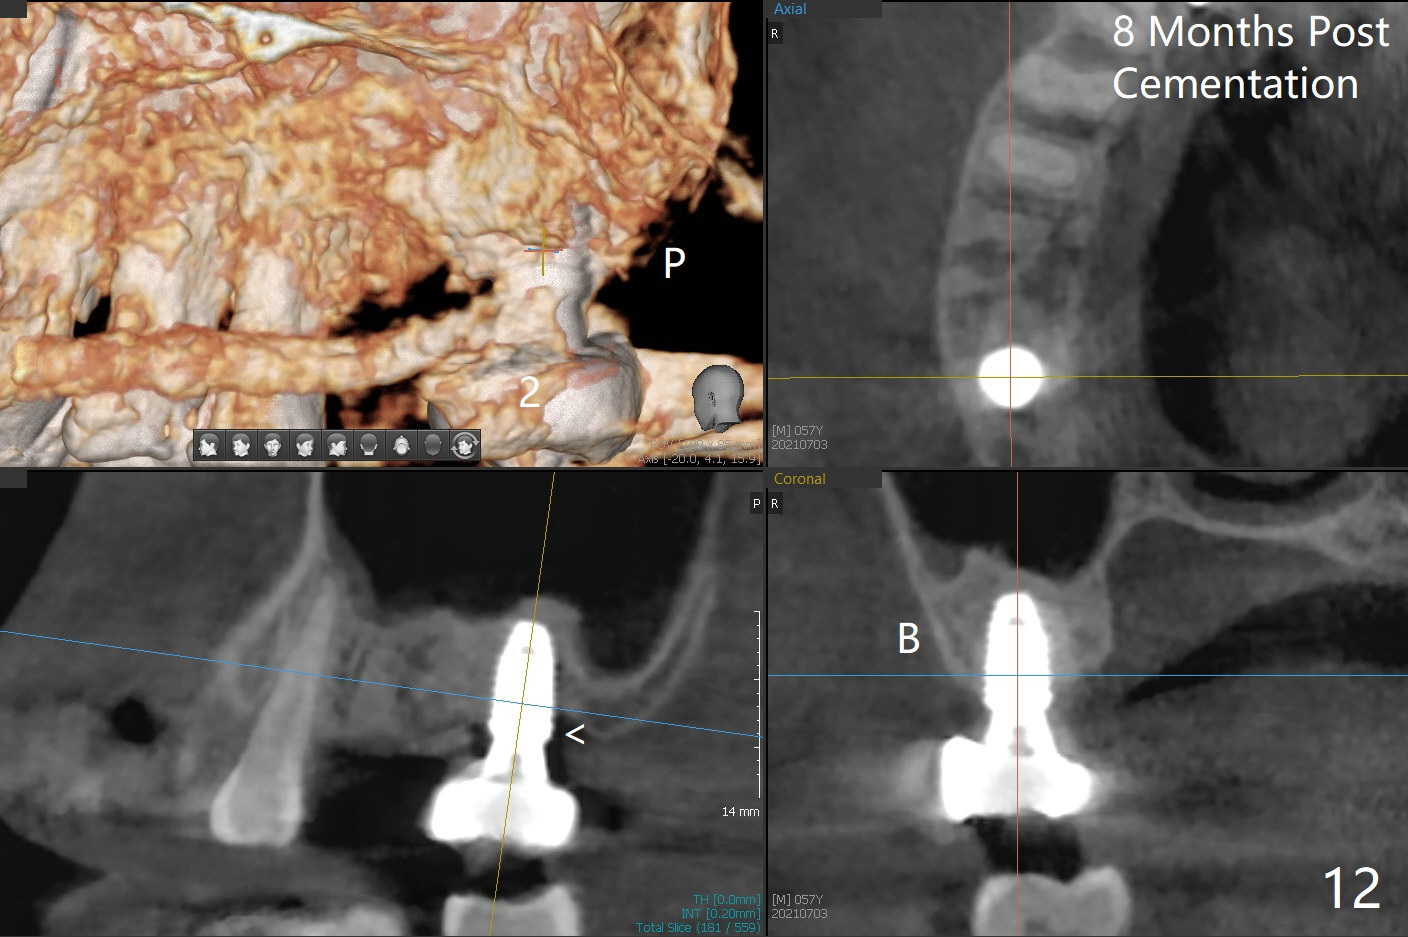

牙冠粘固后8个月,2号牙植体远中骨质吸收(图十二:<)。